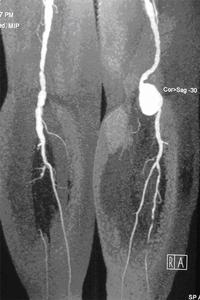

臍周或左上腹部出現膨脹性搏動的腫塊,是腹主動脈瘤臨床診斷的主要依據。原有腹部搏動性腫塊病史,當出現前述症狀時,即應考慮腹主動脈瘤合併內 瘺、破裂出血、遠端動脈栓塞等診斷。下列檢查有助於診斷和鑑別診斷:①超聲檢查:可以描記瘤體的大小及瘤壁有無粥樣斑塊及附壁血栓,尤其適用於腎動脈下腹主動詠瘤的檢查。②腹主動脈造影或數字減影血管造影(DSA):可以檢測腹主動脈瘤的大小、范 圍,腹主動脈主要分支是否累及,為確定診斷及決定手術方案提供依據。③CT檢查:可以同時現察是否存在夾層動脈,動脈瘤與周圍臟器間關係,排除腹腔內其他臟器的疾病。